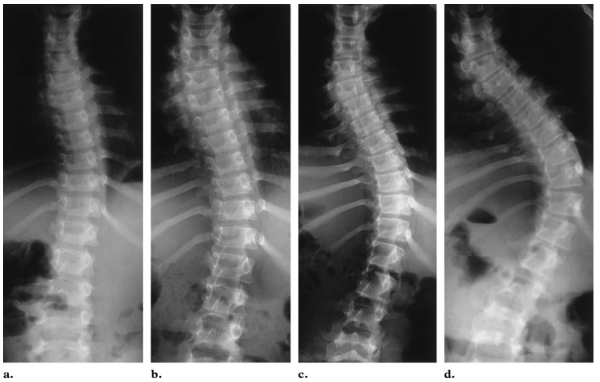

''Omurga diziliminde bozukluk, omuz dengesizliği, belde asimetri ve kalça kemiklerinin birinde öne çıkıklık en sık saptanan bulgulardır. Daha küçük yaşlarda görülen skolyoz genellikle doğumsal problemlere bağlıdır ve hızlı ilerler. Bu çocuklarda, sırtta görülen gamze ve renk değişiklikleri ve sırtta kıllanma en sık görülen bulgulardır.'' dedi.

''Vücut ergonomisi için çok önemli olan bu fizyolojik eğriliklerin ilk görülme yaşları çocuğun ilk ayağa kalkma yaşlarıdır. Bebekler, çocuklar ve erişkinlerde ön ve arkadan omurganın dümdüz görünmesi, sağ ya da sol tarafa eğik olmaması gerekir.''